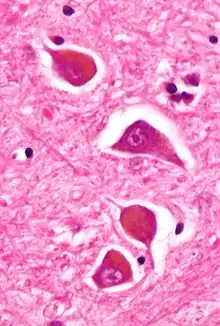

| Micrograph of Alzheimer type II astrocytes, as may be seen in hepatic encephalopathy | |

There are various explanations why liver dysfunction or portosystemic shunting might lead to encephalopathy. In healthy subjects, nitrogen-containing compounds from the intestine, generated by gut bacteria from food, are transported by the portal vein to the liver, where 80–90% are metabolised through the urea cycle and/or excreted immediately. This process is impaired in all subtypes of hepatic encephalopathy, either because the hepatocytes (liver cells) are incapable of metabolising the waste products or because portal venous blood bypasses the liver through collateral circulation or a medically constructed shunt. Nitrogenous waste products accumulate in the systemic circulation (hence the older term "portosystemic encephalopathy"). The most important waste product is ammonia (NH3). This small molecule crosses the blood–brain barrier and is absorbed and metabolised by the astrocytes, a population of cells in the brain that constitutes 30% of the cerebral cortex. Astrocytes use ammonia when synthesising glutamine from glutamate. The increased levels of glutamine lead to an increase in osmotic pressure in the astrocytes, which become swollen. There is increased activity of the inhibitory γ-aminobutyric acid (GABA) system and the energy supply to other brain cells is decreased. This can be thought of as an example of brain edema of the "cytotoxic" type.[13]